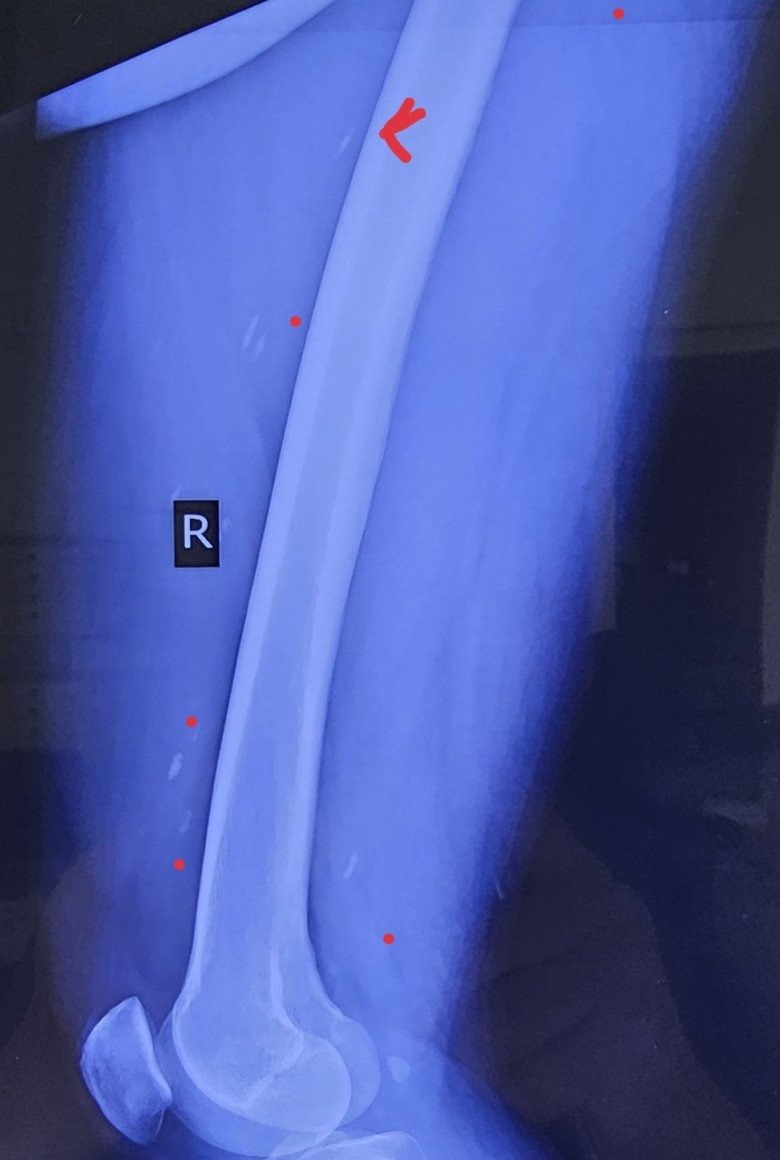

Bác sĩ thăm khám phát hiện người đàn ông nhiễm nhiều loại giun sán, đặc biệt là sán dây. Kết quả chụp X-quang thấy có rất nhiều sán nằm ở các cơ. Bệnh nhân nói có sở thích ăn những món tái, sống như gỏi cá, rau sống và tiết canh. Trước đó, anh đã có 3 đợt điều trị sán cơ và sán não.